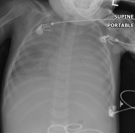

This was his chest x-ray

In May 2007 he represented with one week of fever, increased work of breathing and dry cough. He had respiratory difficulty with hypoxia. The Chest radiograph showed bilateral infiltrates and he was admitted to the PICU and treated with antibiotics and BiPAP. He was slow to improve with a persistent oxygen requirement. There was concern he had gasto-oesophageal reflux disease with aspiration pneumonitis. A repeat bronchoscopy showed semi-opaque milky aspirates. The pathology report was of a proteinaceous debris admixed with macrophages. Rare groups of likely reactive epithelial cells and cholesterol type clefts were also noted. It was Periodic Acid Schiff (PAS) positive debris with a few lipid laden macrophages.